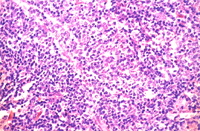

組織病變: 肺臟部份區域可見圍小支氣管及圍血管周圍淋巴組織增生(圖3),這些細胞以淋 巴球及少量巨噬細胞和漿細胞為主(圖4)。

其它病變可見第二型肺泡細胞增生,小支氣管上皮細胞肥大增生,小支氣管擴張, 肺泡間隔淋巴球及漿細胞等浸潤。

黴漿菌症為大小鼠首要病原,而且可藉由空氣或接觸感染,一旦發生,其難滅絕。 黴漿菌有20多種血清型,而一般會造成人或囓齒類感染為:M. collis : 非致病性,存在於大小鼠之鼻咽部及結膜,亦有報告指出會造成生殖道感染。 M. arthritidis : 大鼠關節炎。 M. neurolyticum : 小鼠旋轉病。 M. pulmonis : 鼠類及兔子重要呼吸道傳染性病原。為大小鼠首要呼吸道病原其鑑別診斷見表一。 M. pneumoniae : 人類非典型肺炎。 M. hominis : 人類婦女生殖道感染。 而人鼠之間不同的黴漿菌亞型,一般而言並不會互相感染,亦即並非人畜共通疾病。 大鼠對黴漿菌較敏感,而報告指出不同的菌種中以上M. pulmonis 具顯著呼吸道致病性。患鼠出現體重減輕、呼吸困難或呼吸道震顫聲。一旦環境中氨濃度高過25ppm以上或病毒(Sendai,MHV)合併感染則會加重黴漿菌感染之疫情。感染途徑可經空氣傳播、子宮感染及接觸等方式。臨床症狀有時在感染後 3~6個月才出現。病變一般呈不顯性或輕度症狀,鼻腔、呼吸道、中耳、子宮是檢查重點。肉眼可見化膿性鼻炎、肺前腹端肝變、支氣管擴張、肺膿瘍或中耳炎。組織相特徵為呼吸道上皮細胞扁平化生,纖毛消失,感染鼻腔黏膜及咽上皮細胞出現聚合細胞(syncytia),肺臟圍支氣管及圍血管周圍淋巴球及漿細胞增生,慢性小支氣管炎,小支氣管擴張,化膿性中耳炎。

而大鼠肺臟之支氣管圍管現象是以淋巴球為主,而小鼠則以漿細胞為主,此點為其 不同。裸鼠鼻腔接種M. pulmonis會發病造成關節炎,一般小鼠則不會。此為證明黴漿菌感染方法之一。